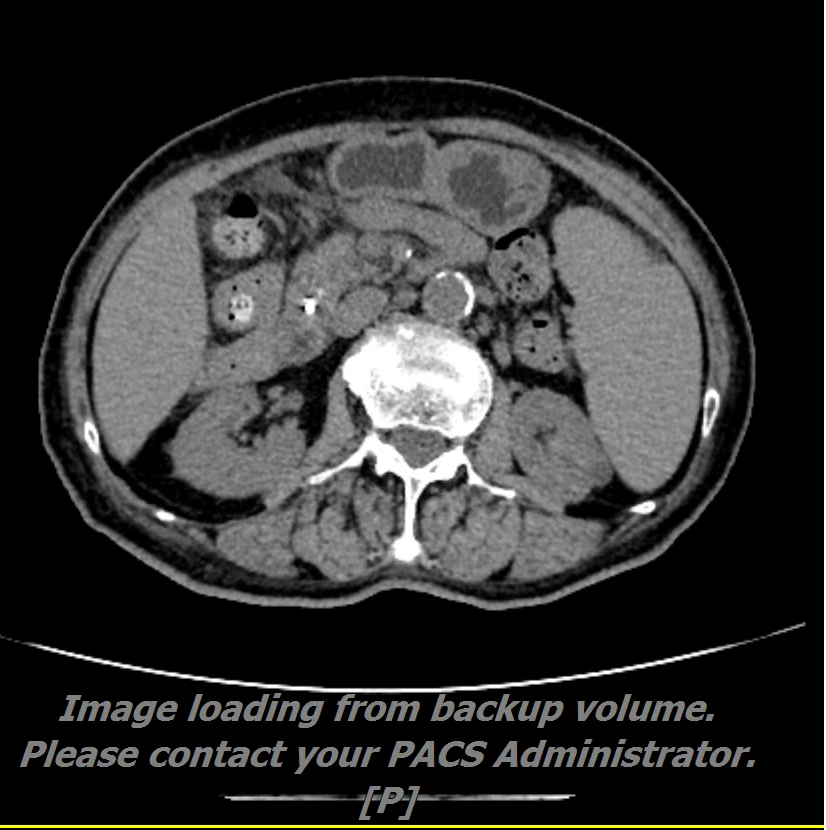

患者,女,60岁,主因“间断后背部胀痛1月。”2022-02-21就诊中国人民解放军中部战区总医院行腹部CT示:胰腺颈体部占位性病变并胰腺体尾部萎缩、胰管扩张,局部增大淋巴结,考虑胰腺癌可能;CA199 >1000U/ml;腹部核磁示:胰颈部占位性病变,考虑恶性肿瘤,胰腺Ca可能大,腹腔干、脾动脉、肝总动脉局部包绕其中,与门静脉边界欠清,胰体尾部萎缩、胰管扩张;胰头周围数枚淋巴结显示,部分增大,考虑转移。为进一步明确诊断,我院消化内三科为患者行超声胃镜检查及穿刺示:于胰颈部可见一2.5×3.0cm大小不规则低回声占位,肠系膜上静脉穿入其中,弹性成像提示:病变部分 略偏硬。胰腺体尾部胰管扩张,最宽处约3mm。超声穿刺病检结果示:(胰体占位穿刺组织)腺癌。在明确诊断前提下,碳离子治疗+化疗治疗;让“癌中之王”不再坐以待毙。